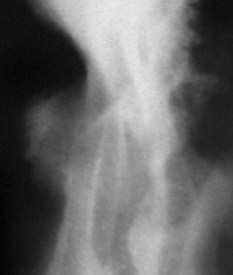

При детальной оценке контуров «контур – ниши», контуры её довольно ровные, четкие. Определяется некоторая неровность в области дна, что, по всей видимости, обусловлено наличием сгустка крови или некротических масс – иллюстрации – 3, 4.

3.